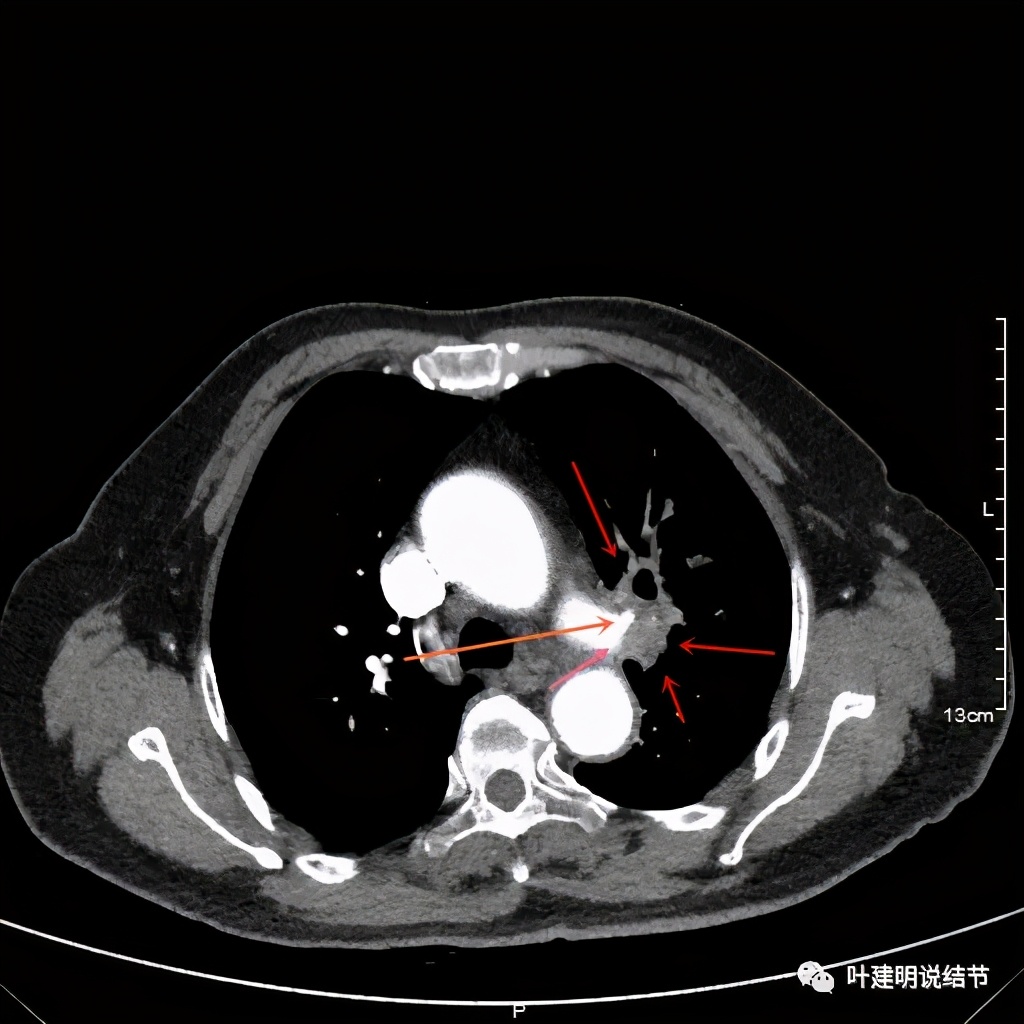

患者手术安排在2021.6.21进行,手术组先胸腔镜进胸探查有无胸壁转移及胸水,评估手术切除的可能性,并在镜下游离下肺韧带、清扫纵隔淋巴结,解剖游离上肺静脉,并将左肺动脉主干游离出来并套阻断带备用,以防解剖过程中出血时控制肺动脉出血。因肺门部原肿瘤部位仍与叶间动脉及上叶支气管、肺动脉分支等愈着紧密:

上图红色箭头示肿瘤,桔色示肺动脉及其分支,仍关系紧密

上图示肺动脉仍与软组织影关系密切,没有间隙可分开

上图示肺动脉与肿瘤的关系仍紧密

上两图示叶间肺动脉的上缘与肿瘤没有界限